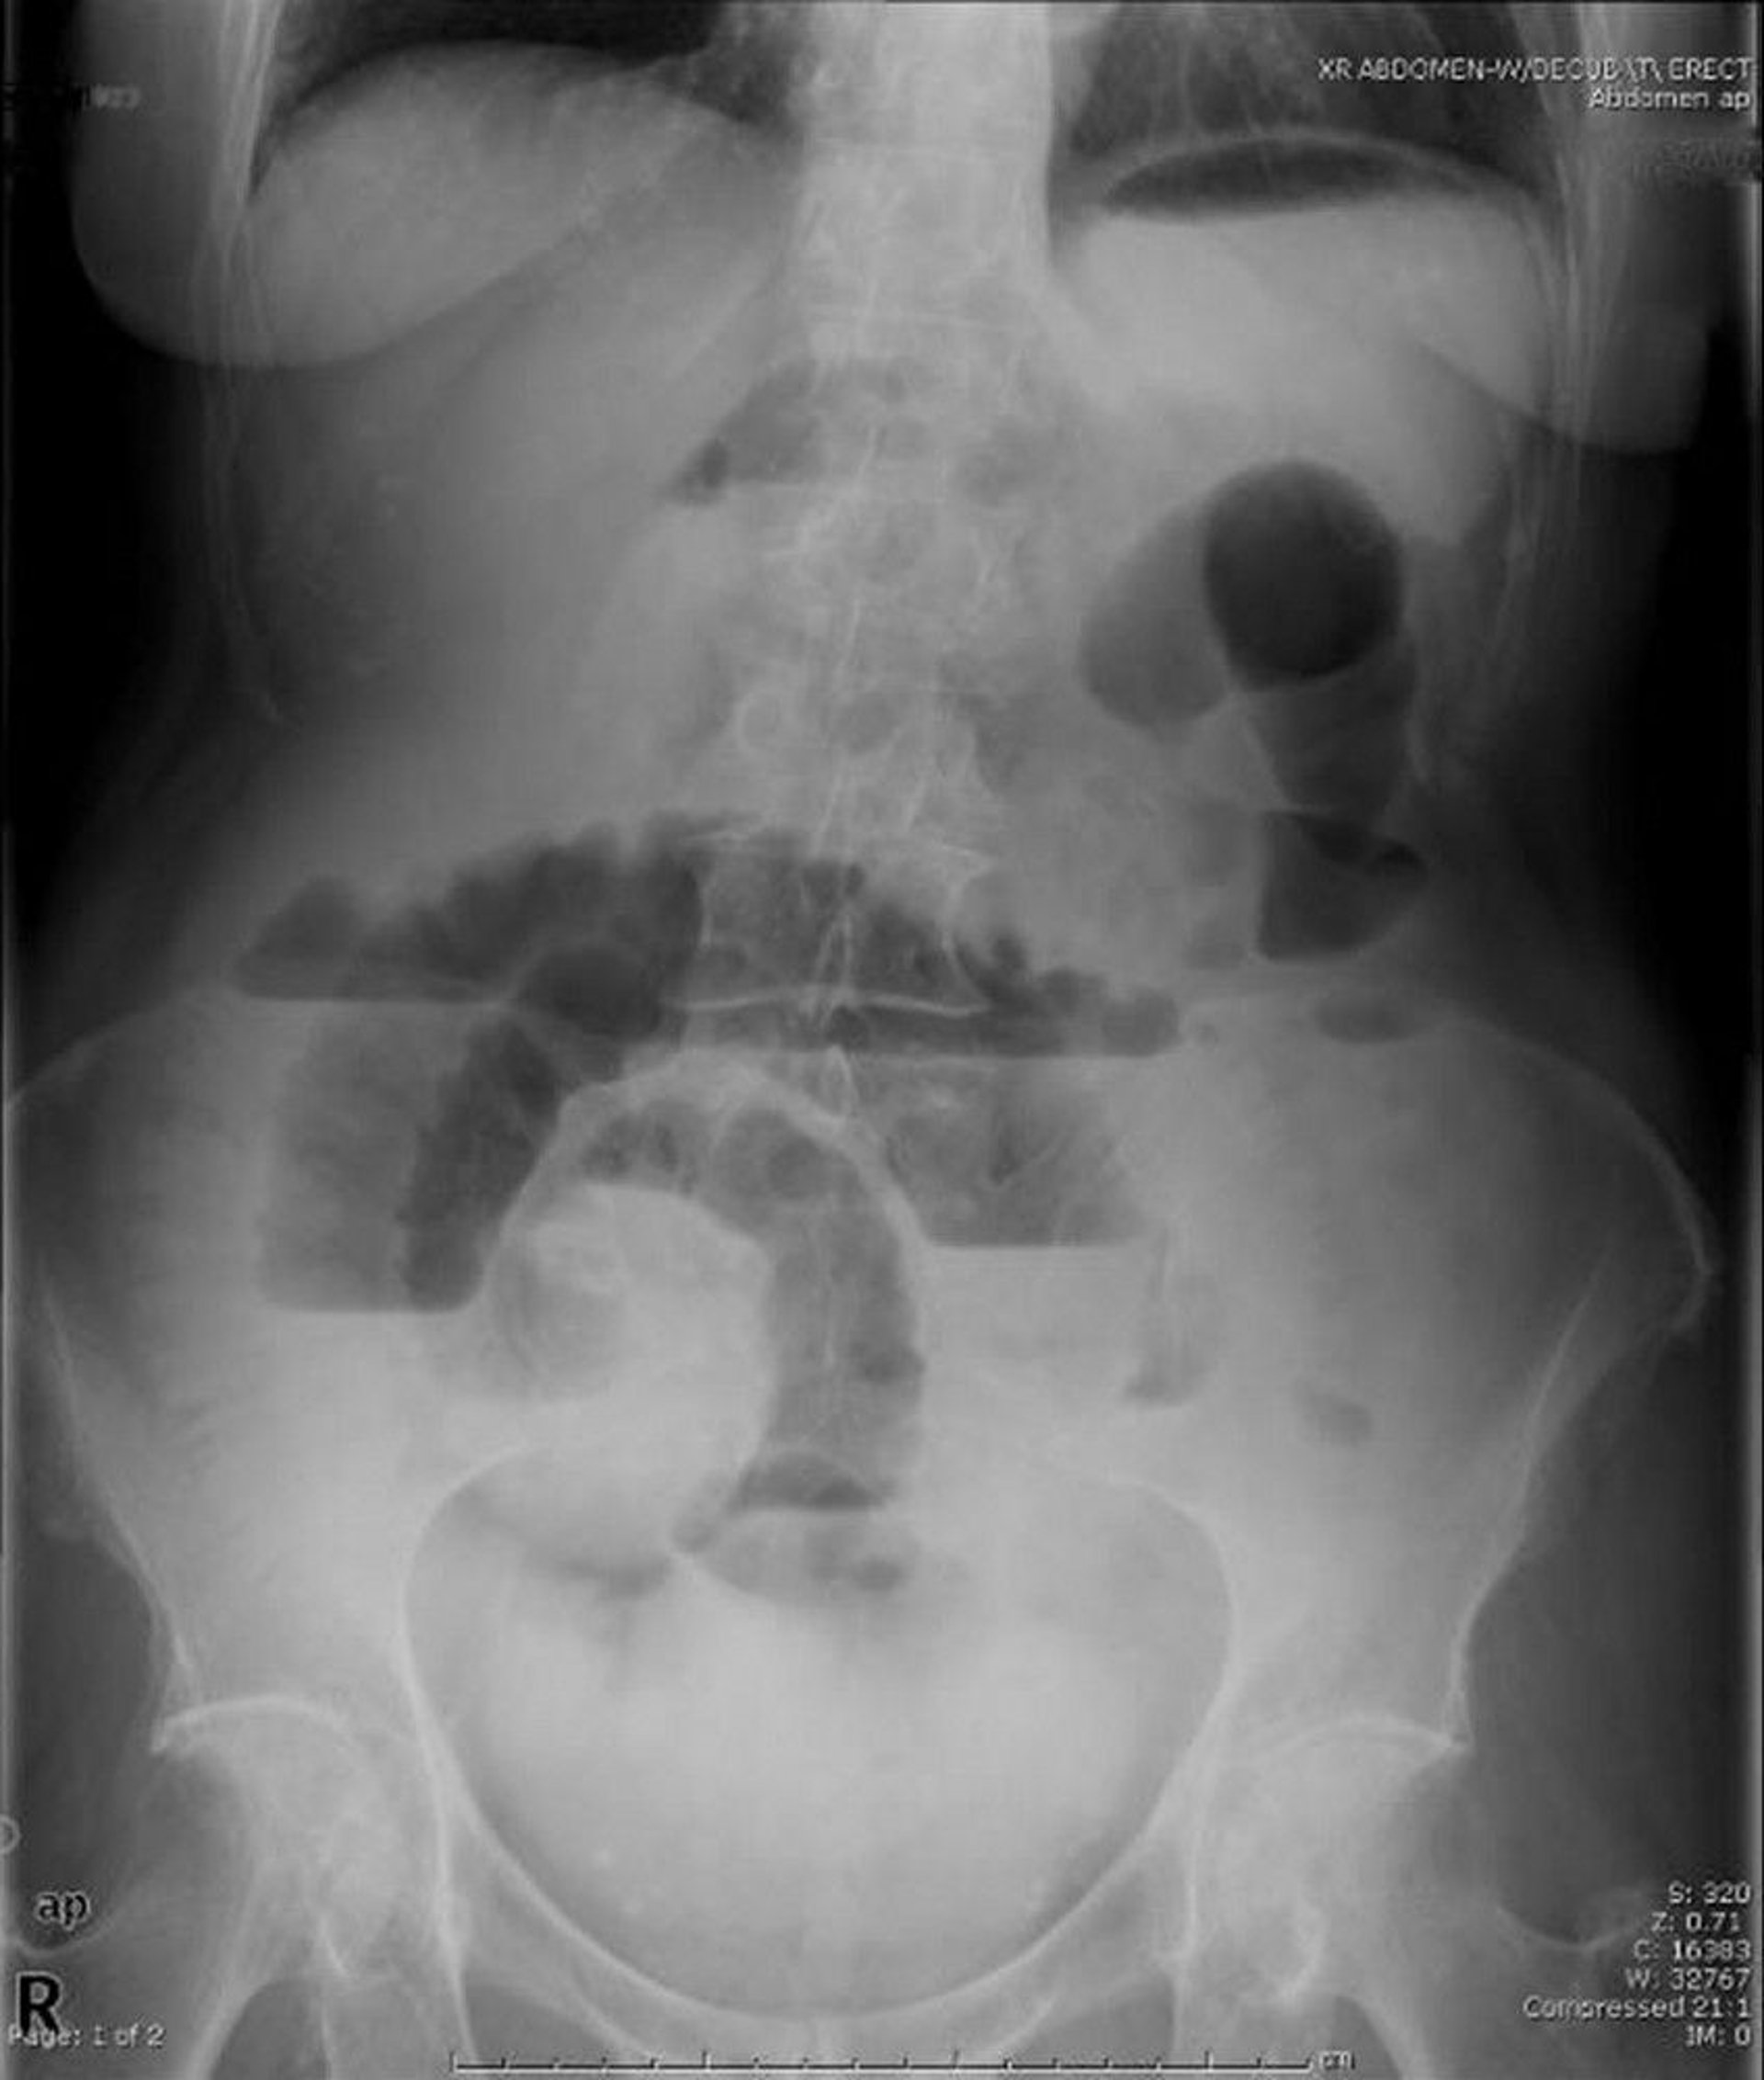

Small-Bowel Obstruction (Upright Radiograph)

This upright abdominal radiograph shows obstruction of the small bowel. Note the multiple air-fluid levels.

Image provided by Parswa Ansari, MD.